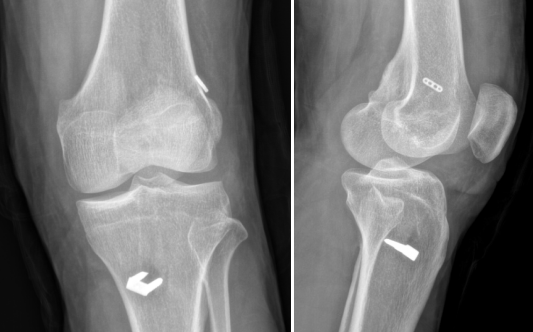

术后复查X片